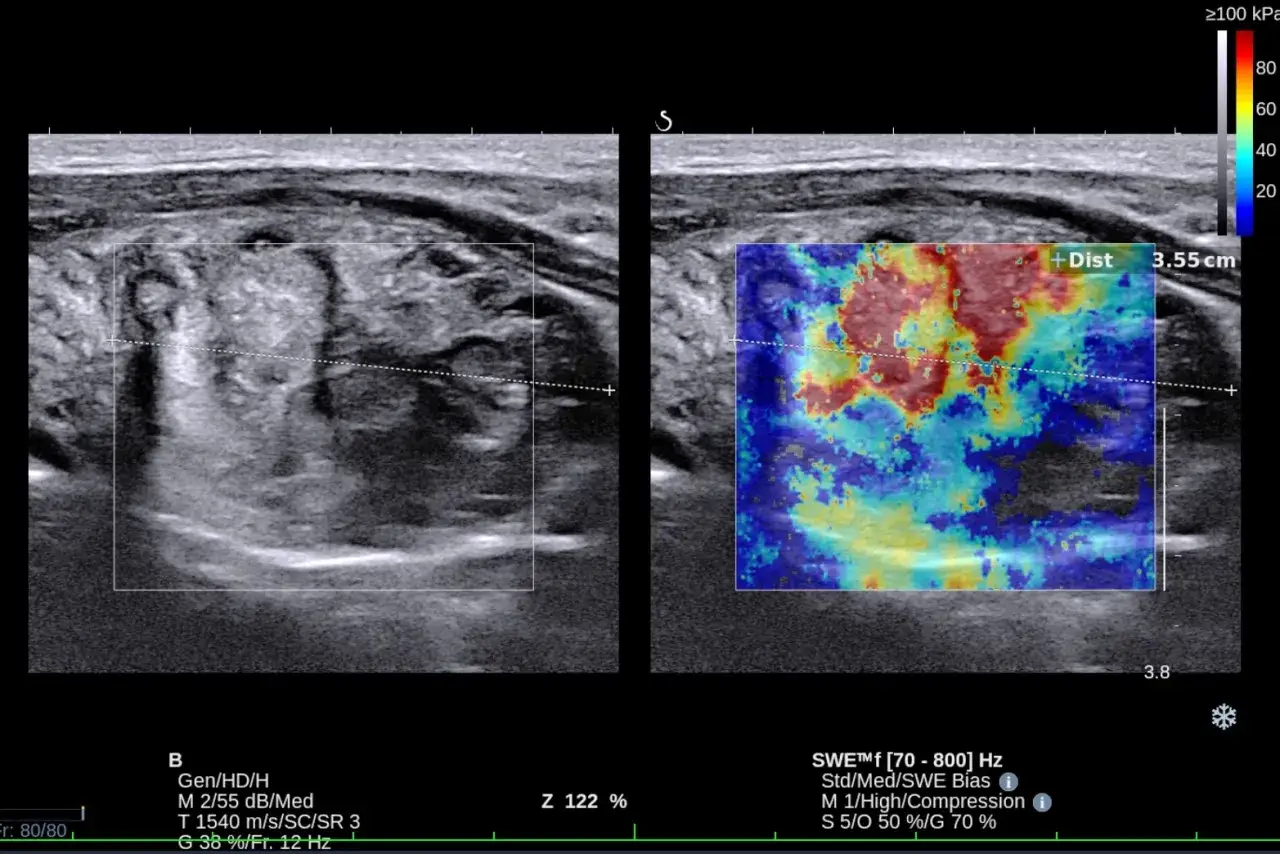

Badania laboratoryjne, takie jak oznaczenie poziomu TSH (hormonu tyreotropowego), są niezwykle ważne w diagnostyce chorób tarczycy, jednak często nie dostarczają pełnego obrazu stanu gruczołu. Ultrasonografia (USG) stanowi cenne uzupełnienie, pozwalając na ocenę morfologiczną tarczycy jej wielkości, kształtu, jednorodności miąższu oraz obecności ewentualnych zmian ogniskowych, takich jak guzki czy torbiele. Jest to badanie nieinwazyjne i bezbolesne. Aby uzyskać jak najbardziej wiarygodny wynik, nie jest wymagane specjalne przygotowanie. Warto jednak ubrać się w luźne ubranie, które nie uciska szyi, a także poinformować lekarza o wszystkich przyjmowanych lekach, zwłaszcza tych wpływających na pracę tarczycy.

Echogeniczność to termin określający, jak struktury odbijają fale ultradźwiękowe. Prawidłowy miąższ tarczycy powinien być normoechogeniczny (czyli mieć średnią echogeniczność) i jednorodny. Jeśli opis wskazuje na echogeniczność niejednorodną lub hipoechogeniczną (czyli obniżoną), może to sugerować obecność stanu zapalnego w tarczycy, na przykład w przebiegu choroby Hashimoto. Tkanka zmieniona zapalnie inaczej odbija fale ultradźwiękowe.

Badanie z użyciem Dopplera ocenia przepływ krwi w tarczycy. Unaczynienie prawidłowe oznacza, że przepływ krwi jest w normie. Natomiast unaczynienie wzmożone, czyli zwiększona ilość naczyń krwionośnych lub intensywniejszy przepływ, może być związane z procesami zapalnymi lub nadczynnością tarczycy.

W opisie USG mogą pojawić się również informacje o mikrozwapnieniach lub zmianach ogniskowych, takich jak guzki czy torbiele. Mikrozwapnienia, czyli bardzo drobne złogi wapnia, mogą być niekiedy markerem zwiększonego ryzyka złośliwości zmiany i wymagają szczególnej uwagi. Podobnie, obecność guzków czy torbieli, zwłaszcza jeśli są duże, szybko rosnące lub mają niepokojące cechy w obrazie USG, może wymagać dalszej diagnostyki, takiej jak biopsja cienkoigłowa (BAC) lub regularna obserwacja.